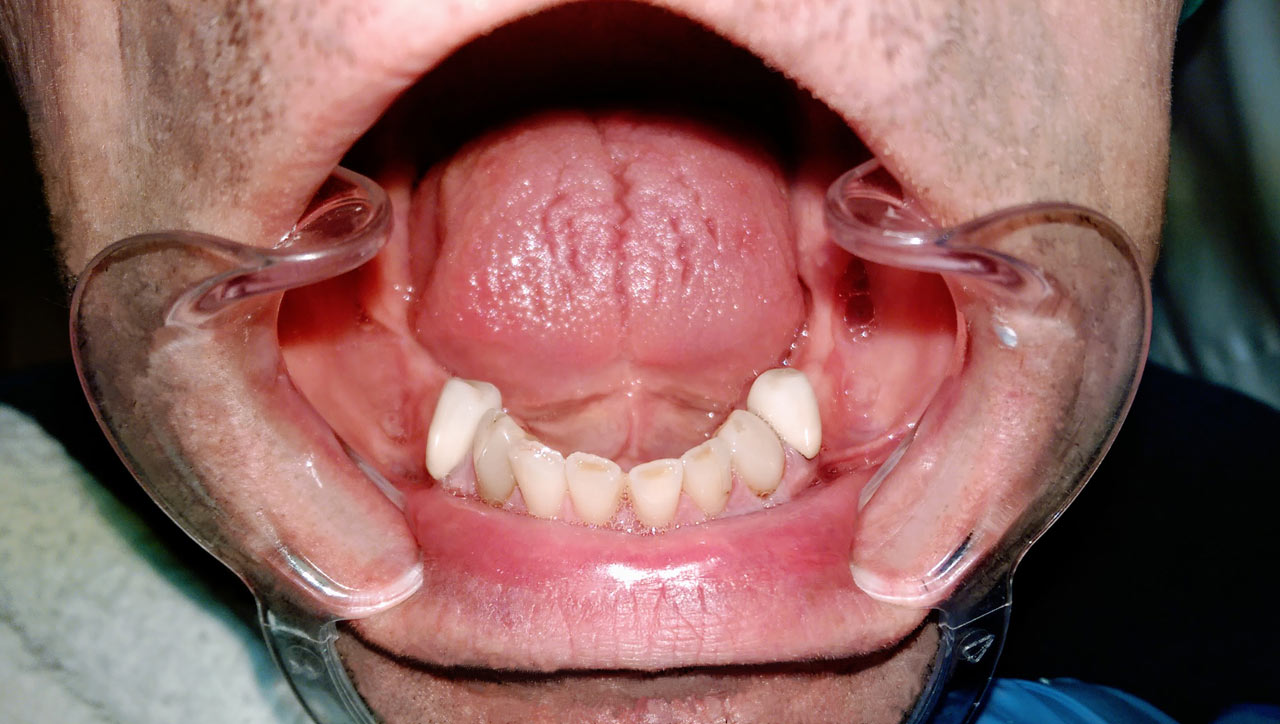

Teljes fogatlanság helyreállítása 2 nap alatt

Teljes fogatlanság helyreállítása 2 nap alatt azonnal terhelhető svájci IHDE implantátumokkal és PMMA műanyag hidakkal. Intraorális szkennerrel vettünk lenyomatot az implantáció után, és erre a digitális mintára készítette el a fogtechnika a hidak digitális tervezését, majd faragta ki műanyagból. Ezt a gyors munkát az azonnal terhelhető implantátumok és a digitális lenyomat, tervezés segítségével tudtuk megcsinálni mindössze 2 nap alatt. Dr. Kelemen Péter és a Symbion Fogtechnika munkája.